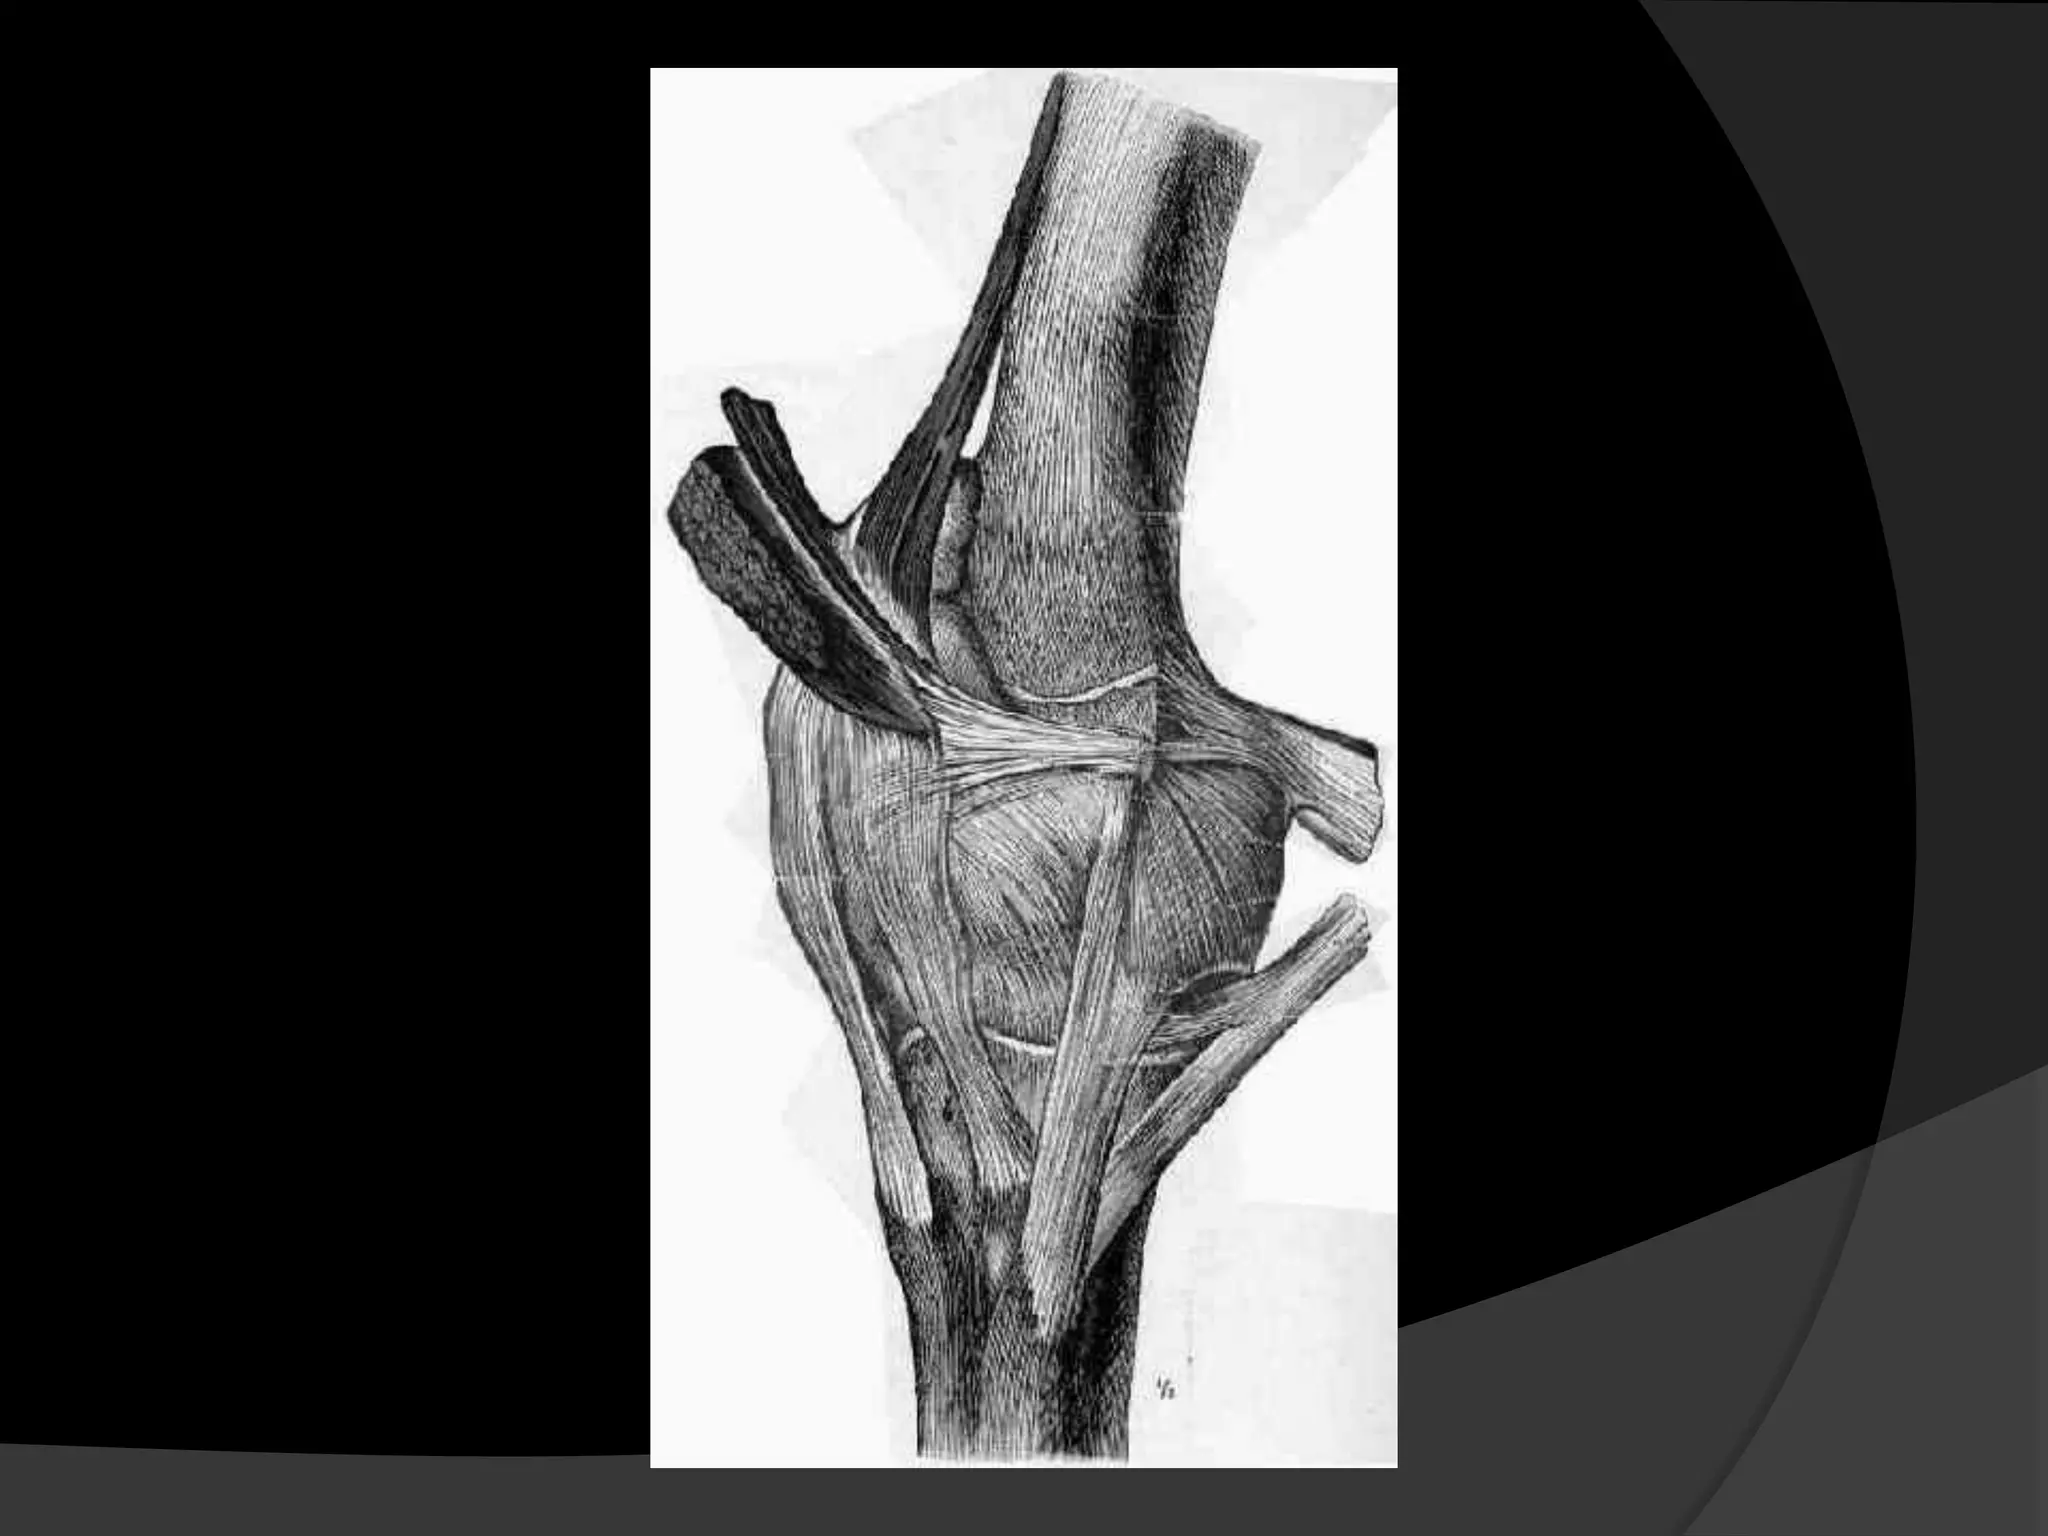

Anatomy

It extends between the superomedial pole

of the patella to the anterior aspect of the

medial epicondyle

The vertical distance from the superior pole

of the patella to the top of the medial

patellofemoral ligament averages about 6.1

mm.

The distal border of the VMO muscle

attaches along the majority of the proximal

medial edge of the MPFL

Steensen RN et al, Am J Sports Med. 2004;32:1509-1513.